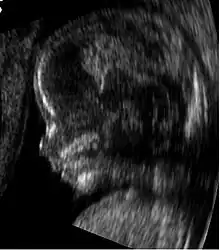

Obstetric sonogram of a fetus at 16 weeks. The bright white circle center-right is the head, which faces to the left. Features include the forehead at 10 o'clock, the left ear toward the center at 7 o'clock and the right hand covering the eyes at 9:00.